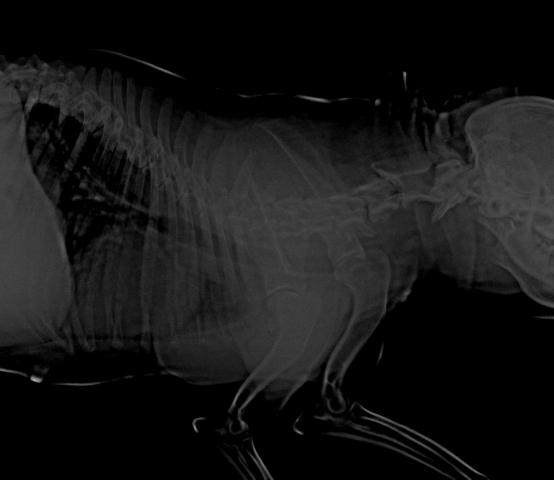

Снимки хорошие, качественные, но совершенно не информативные. На этих пленках патология не определяется. Но здесь нет снимка, который нужен обязательно - поясничный отдел позвоночника в прямой проекции (такой, как 3-й, но только не шея, а поясница).

Нет,наоборот.Собака сначала стала немного наклонять голову вправо.Когда были на консультации у окулиста,то он обратил внимание на это ,сказал,что есть какие-то изменения в области шеи.Я отсутствовала дома 2 недели.Приехала,собаку вообще не узнала.Крен головы вправо стал еще сильнее,передние ноги как-то ослабли.Она идет,может споткнуться,упасть.Сходили,сделали рентген.снимок.Поставили диагноз:атланто-аксиальная нестабильность шейного отдела,спондилоартроз. Проколола 5 дней:актовегин,папаверин,комбилипн,мидокалм,дексаметазон. Пока делала уколы и еще дней 5 после этого собаке стало легче,а потом опять вернулись к тому, что было.На консультации врач сказал,что дальше просто колоть преднизалон. Я уехала к другому врачу,тот сделал снимки,которые я Вам отослала.Сказал, что диагноз не подтверждает,на пальцах показал, что со спинным мозгом все нормально.С помощью какой-то процедуры (бумаги на работе)обнаружил перфорацию барабанной перепонки.Выписал лечение:цефтриаксон,циклоферон,цебролизин(колола 2 дня,стало хуже),комбилипен.В уши-изотик.Сказал,что может быть у собаки был инсульт.Собаке от лечения хуже.Вот такие дела.